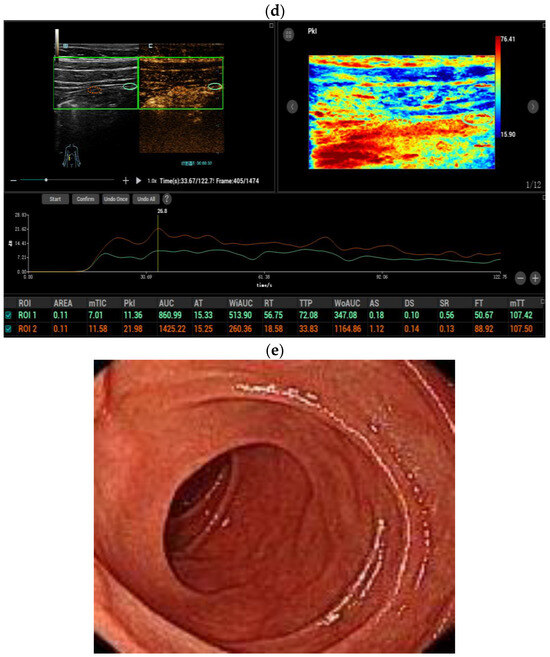

| Color Doppler signal | <0.001 * | ||

| Limberg 0 | 0 | 6 (46.1%) | |

| Limberg I | 5 (12.8%) | 3 (23.1%) | |

| Limberg II | 22 (56.4%) | 4 (30.8%) | |

| Limberg III | 7 (18.0%) | 0 | |

| Limberg IV | 5 (12.8%) | 0 | |

| CEUS enhancement | <0.001 * | ||

| Pattern I | 24 (61.5%) | 1 (7.7%) | |

| Pattern II | 10 (25.6%) | 3 (23.1%) | |

| Pattern III | 5 (12.8%) | 8 (61.5%) | |

| Pattern IV | 0 | 1 (7.7%) | |